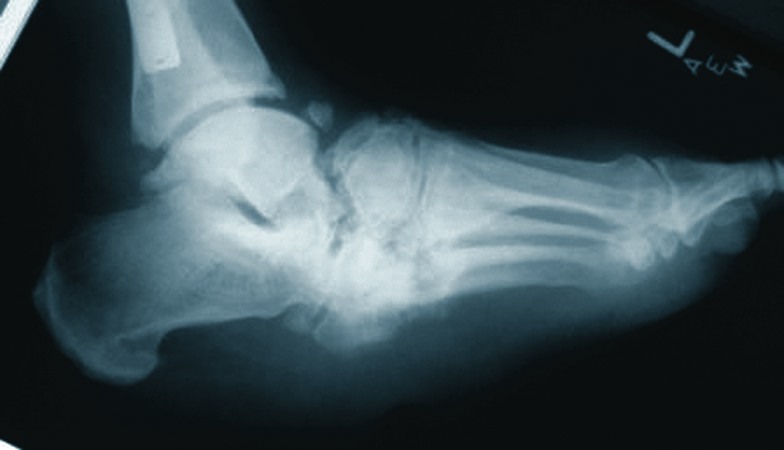

In this case, the patient presented with an end-stage Charcot midfoot with a chronic plantar ulceration and equinus deformity (see photo on the right). The correction entailed midtarsal joint arthrodesis, tendo-Achilles lengthening and local wound care.

Prior to compression of the limited internal beam construct, there were large osseous deficits in the talonavicular joint and calcaneocuboid joint once the surgeon debrided all of the non-viable reactive bone from the midtarsal joint.

Biologic and biophysical enhancement included an external bone stimulator, external fixation and tricalcium phosphate mixed with platelet gel concentrate and DBM. Final consolidation is evident at five months post-op (see photo on the left).